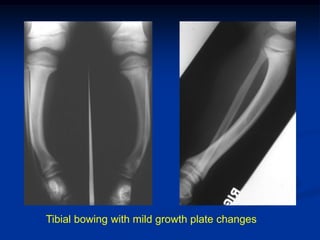

Case #2       X-linked Hypophosphatemic Rickets

7 year male from a family of short

stature and bowed lower extremities

Tibial bowing with mild growth plate changes